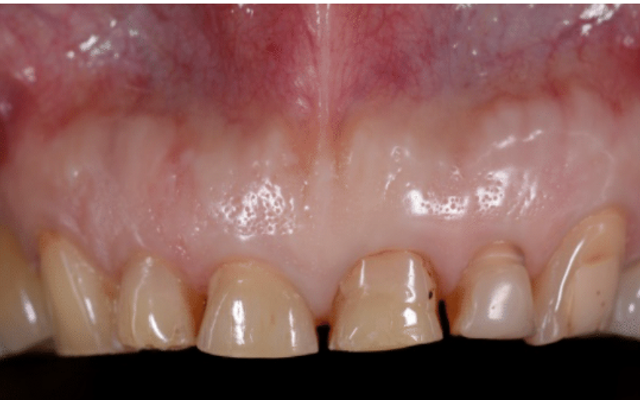

Crown lengthening can also be carried out for cosmetic reasons to expose more tooth structure to improve the appearance of the teeth or to reposition the gum tissues to an aesthetically acceptable position. This is a procedure that is often required where a patient has a “gummy smile” to reduce the amount of gum that is showing (Figure 9D, 9E and 9F).

Patient has worn their teeth down and has insufficent tooth structure for restoration with crowns.